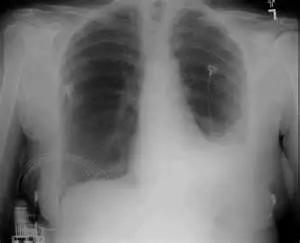

下圖為開心手術後病患的胸腔 X 光片,應加強下列何項物理治療?

- 胸腔 X 光 (CXR) 判讀:

- 左下肺野 (Left Lower Lung Field):出現大片的白色致密陰影 (Opacity),這導致左側橫膈膜邊界 (Diaphragm border) 和左心緣 (Left heart border) 模糊不清(Silhouette sign)。這是典型左下肺葉塌陷 (LLL Atelectasis) 的表現,也可能伴隨部分肋膜積水 (Pleural effusion)。

- 右肺野:相對清晰,無明顯塌陷。

- 手術痕跡:雖影像解析度有限,但結合題幹「開心手術後」,正中胸骨處應有胸骨鋼絲 (Sternal wires),且術後傷口疼痛會限制病患的深呼吸能力。

- 臨床意義:影像顯示明顯的局部肺容積減少(塌陷)。治療重點應針對該區域(左下